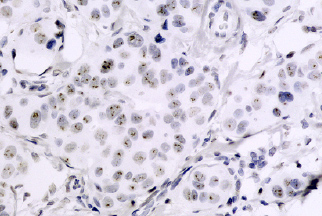

A Hibridização “in situ” Cromogênica (CISH – Chromogenic In Situ Hybridization) é importante método de Patologia Molecular para detectar alterações genéticas em associação com a morfologia celular, particularmente detecção de genoma de vírus (HPV e EBV), que podem ser importantes para o diagnóstico, prognóstico e orientação terapêutica não apenas de doenças infeciosas, mas também de algumas neoplasias, tais como linfomas e o câncer de colo uterino.

É um método de patologia molecular caracterizado pela identificação e localização de ácidos nucléicos alvo (sequências de DNA ou RNA), através da ligação complementar de sondas (sequências de DNA conhecidas, geralmente obtidas comercialmente) marcadas com moléculas cromogênicas, permitindo identificações de material genético em células através da observação em microscópio óptico convencional.

A realização das técnicas e estudo dos casos são realizados com suporte de laboratório externo. O caso é posteriormente revisão pelo médico patologista do Instituto antes da emissão do laudo.